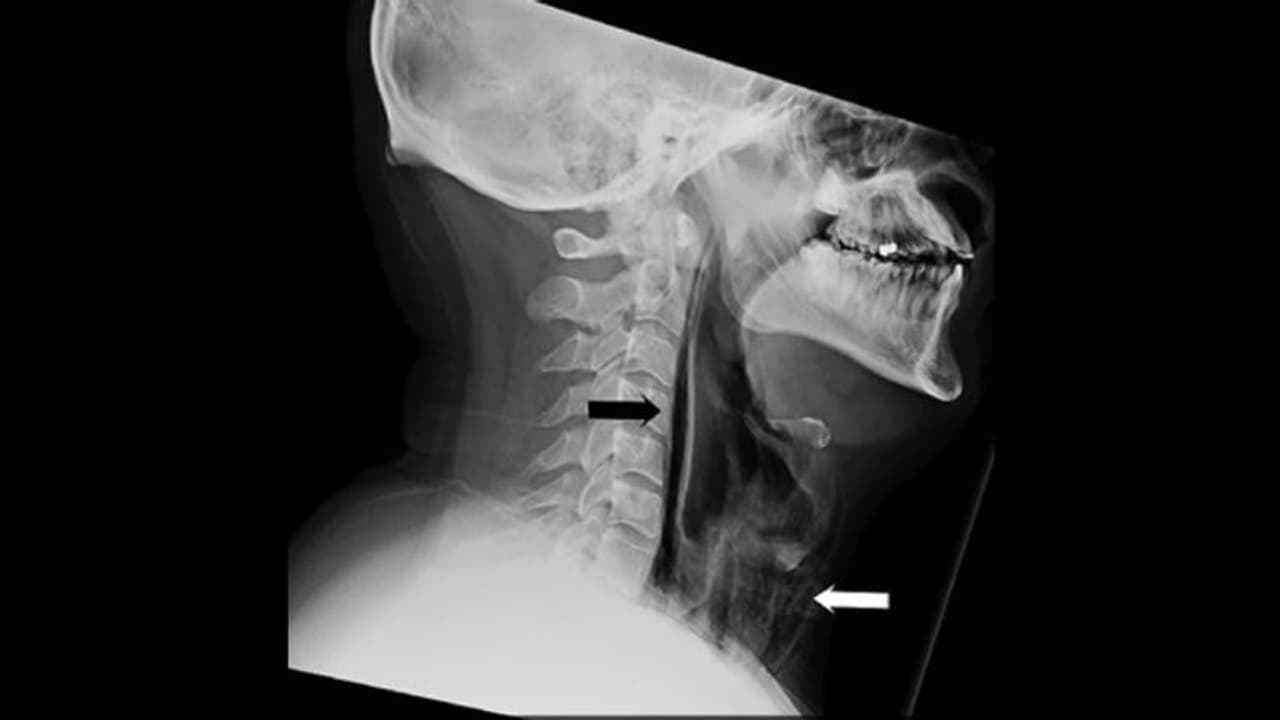

దీంతో అతనికి వాయినాళంలో భరించలేని నొప్పితో పాటు.. మెడ రెండువైపులా వాచింది. వెంటనే డాక్టర్ దగ్గరికి పరిగెత్తాడు. వైద్యులకి లోపల నుండి చిన్న శబ్దం వినిపించింది. అయితే అతనికి ఆహారం తీసుకోవడంలోనూ, మాట్లాడడంలోనూ ఎలాంటి ఇబ్బంది ఎదురు కాలేదు. ఆ తర్వాత ఎక్స్ రే తీయ్యగా అతనికి సర్జికల్ ఎంపీసెమా ఉందని తేలింది.

సర్జికల్ ఎంపిసెమా అంటే చర్మం లోతైన కణజాల పొరల్లో గాలి చిక్కుకు పోతుంది. సిటీ స్కాన్ ద్వారా అతని మెడలో మూడు, నాలుగు వెన్నుపూసల మధ్య చీలిక ఉన్నట్లు తేలింది. ముక్కూ, నోరు మూసుకుని తుమ్మును ఆపుకోవడానికి ప్రయత్నించడంతో ఇంత తీవ్రమైన నష్టం జరిగిందని వైద్యులు తెలిచారు. అయితే ప్రస్తుతానికి అతనికి ఆపరేషన్ అవసరం లేదని.. శరీరంలోని అన్ని శరీర ప్రక్రియలు సరిగానే ఉన్నాయని తెలిపారు.